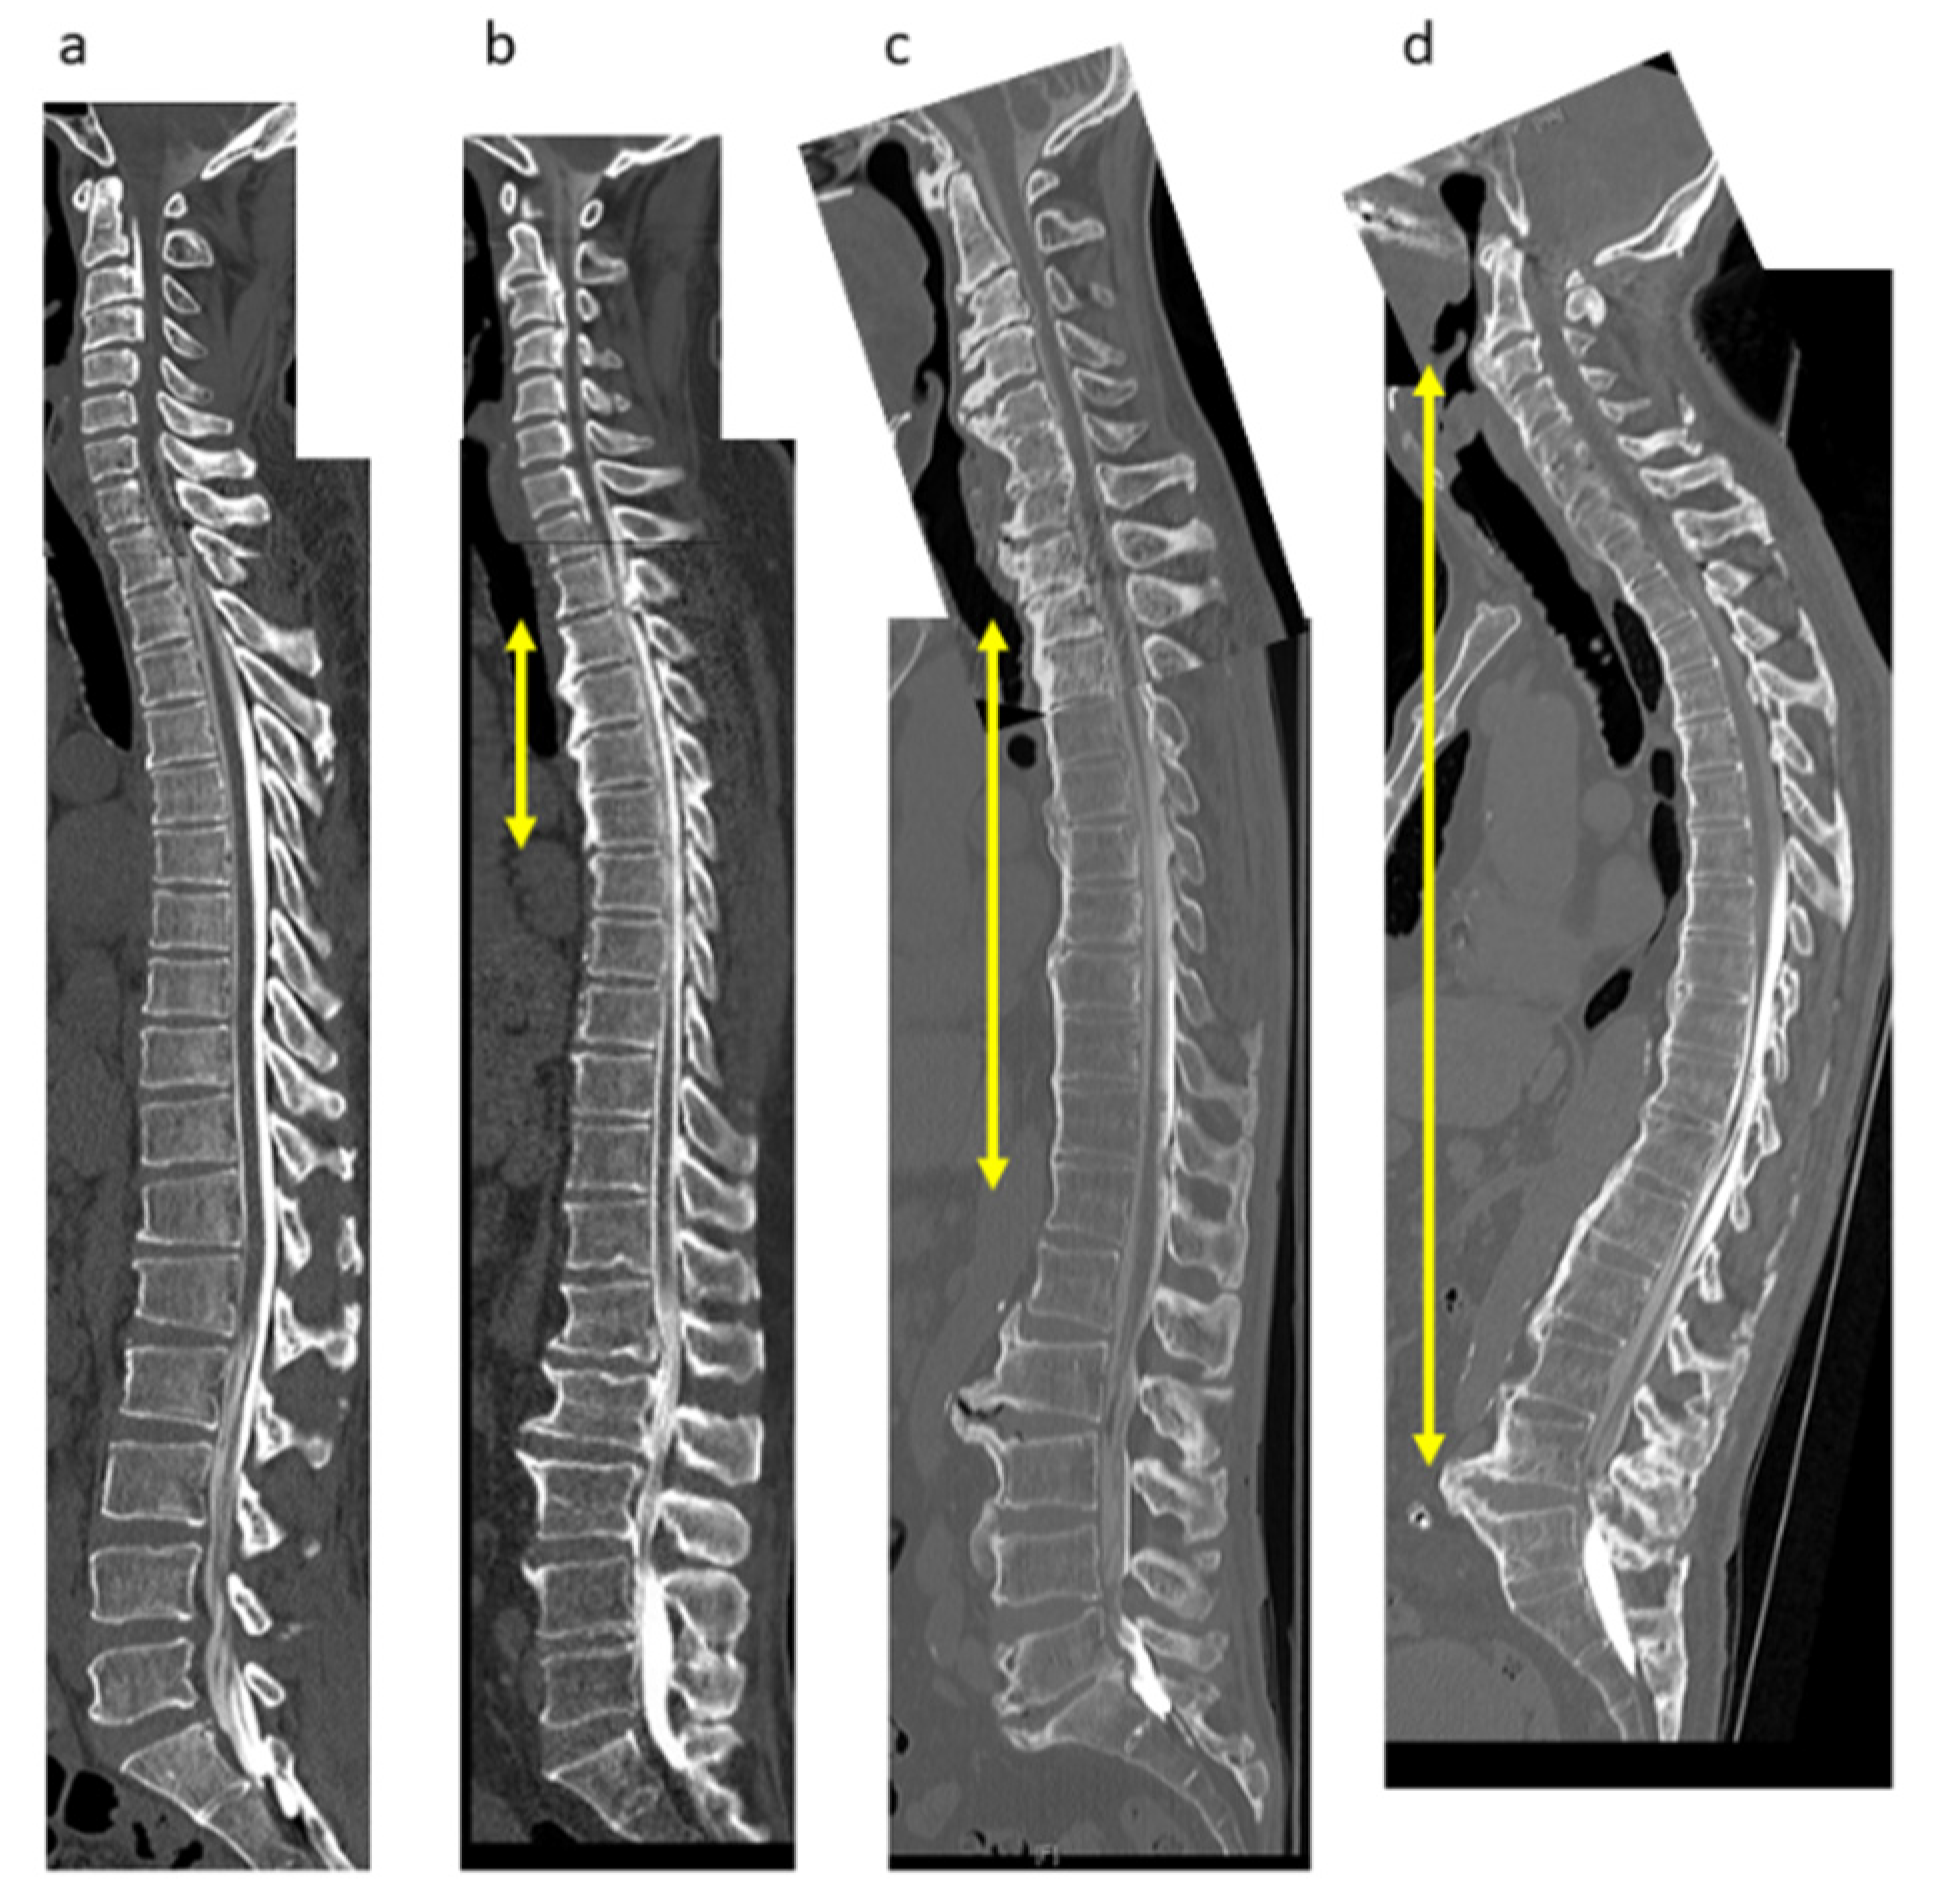

2.3. Radiologic Evaluations